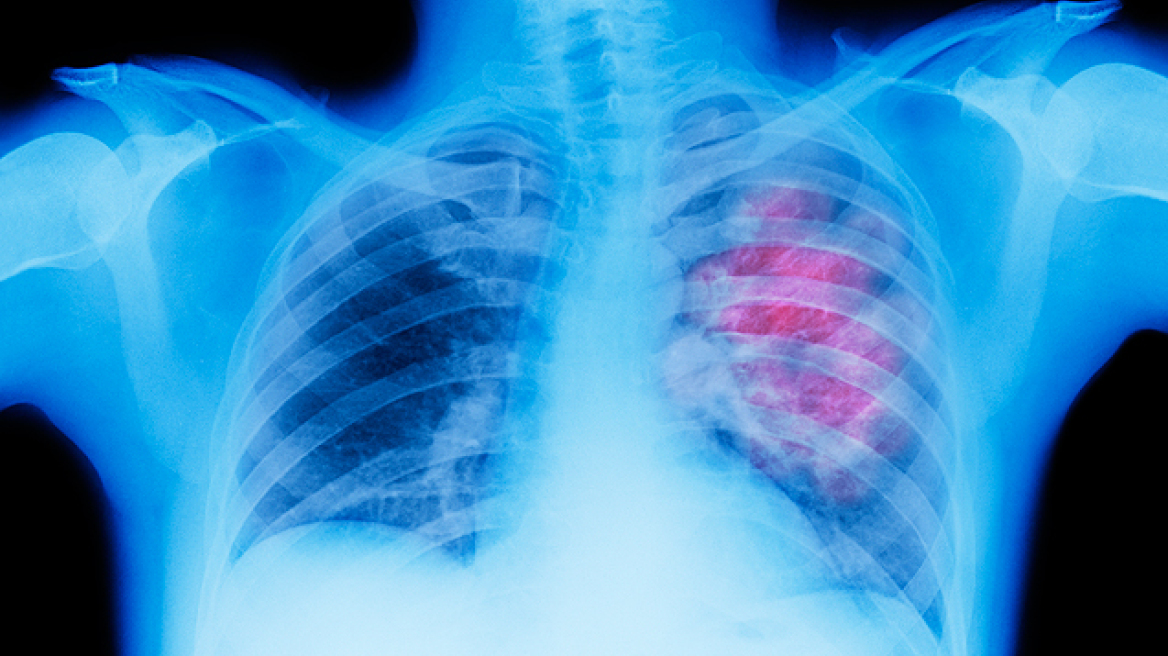

Οι ηλεκτρονικοί υπολογιστές είναι δυνατό να «εκπαιδευτούν» έτσι ώστε να είναι πιο ακριβείς σε σχέση με τους παθολόγους, όσον αφορά την αξιολόγηση των καρκινικών ιστών των πνευμόνων, σύμφωνα με μια νέα αμερικανική επιστημονική έρευνα.

Οι επιστήμονες διαπίστωσαν ότι ένας υπολογιστής με λογισμικό μηχανικής μάθησης μπορεί να διακρίνει ανάμεσα σε διαφορετικούς τύπους καρκίνου των πνευμόνων, καθώς επίσης να κάνει πρόγνωση για την επιβίωση κάθε ασθενούς, καλύτερα από τους γιατρούς που χρησιμοποιούν την κλασική μέθοδο ταξινόμησης των όγκων.

Στον καρκίνο των πνευμόνων όμως το σύστημα αυτό ταξινόμησης δεν είναι πάντα αποτελεσματικό. Οι ερευνητές χρησιμοποίησαν περίπου 2.200 εικόνες από καρκινικούς ιστούς, καθώς επίσης πληροφορίες για το στάδιο κάθε ασθενούς και πόσο έζησε ο καθένας μετά την αρχική διάγνωση, προκειμένου να «εκπαιδεύσουν» ένα πρόγραμμα λογισμικού, ώστε στη συνέχεια αυτό να κάνει τις δικές του -ακόμη πιο ακριβείς- αξιολογήσεις.

Ο υπολογιστής αποδείχθηκε ότι είναι σε θέση να εντοπίσει στις εικόνες των ιστών περισσότερα χαρακτηριστικά σχετικά με τον καρκίνο, από όσα μπορεί να δει το ανθρώπινο μάτι, ακόμη και το έμπειρο. Συνολικά, το ειδικό λογισμικό μπορεί να ανιχνεύσει σχεδόν 10.000 διαφορετικά καρκινικά χαρακτηριστικά, έναντι μερικών εκατοντάδων που «πιάνουν» οι γιατροί. Για παράδειγμα, ο υπολογιστής είναι ικανός να διακρίνει το σχήμα και την υφή του κυτταρικού πυρήνα, καθώς και τις αποστάσεις ανάμεσα στα γειτονικά καρκινικά κύτταρα, πράγματα αδύνατα για το ανθρώπινο μάτι.